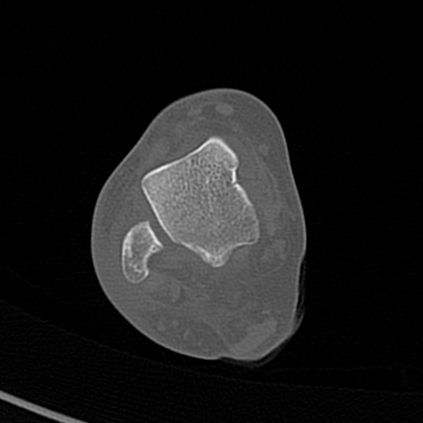

CT reconstruction provides radiologists with images for diagnosis and treatment, yet current deep learning methods are typically limited to specific anatomies and datasets, hindering generalization ability to unseen anatomies and lesions. To address this, we introduce the Multi-Organ medical image REconstruction (MORE) dataset, comprising CT scans across 9 diverse anatomies with 15 lesion types. This dataset serves two key purposes: (1) enabling robust training of deep learning models on extensive, heterogeneous data, and (2) facilitating rigorous evaluation of model generalization for CT reconstruction. We further establish a strong baseline solution that outperforms prior approaches under these challenging conditions. Our results demonstrate that: (1) a comprehensive dataset helps improve the generalization capability of models, and (2) optimization-based methods offer enhanced robustness for unseen anatomies. The MORE dataset is freely accessible under CC-BY-NC 4.0 at our project page https://more-med.github.io/